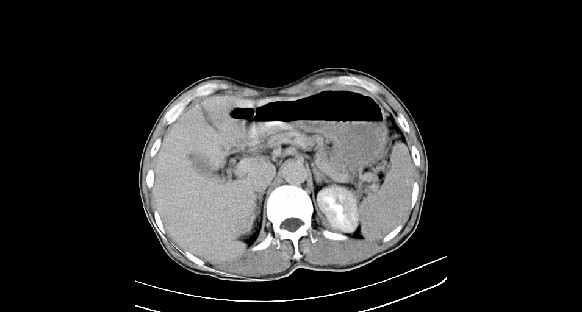

男性,70岁,体检b超发现左肾占位,请各位战友发表一下观点

左肾有两个病灶,且较大的病灶内可见点状钙化灶,增强扫描边缘也是呈渐进性强化,中央部分未见明显强化